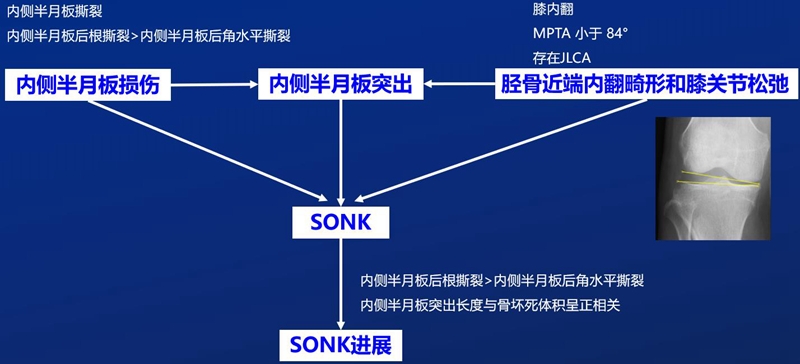

③应力源性理论:

另一项研究纳入26篇文章,其中有21篇(80.7%)涉及半月板在SONK发展中的作用,启示SONK与半月板撕裂或半月板切除术后的发展有关,而内侧半月板撕裂、后根撕裂更常见。

SONK与内侧半月板后根部损伤,有国外学者在SONK患者中通过MRI及关节镜检查,常可发现合并内侧半月板后根部的撕裂,该发生率可达到80%(24/30), 15例完全撕裂,9例部分撕裂。结果表明SONK可能与内侧半月板后根部撕裂后,导致股骨负重区的应力集中、软骨下骨髓水肿有关。

对于半月板损伤类型对SONK的影响,一项研究结果显示内侧半月板后根部撕裂组的半月板突出率为46.1%,平均坏死面积为423.1mm2。内侧半月板后角水平裂组的半月板突出率为35.3%,平均坏死面积为175.8mm2。

与内侧半月板后角水平撕裂相比,后根撕裂将导致更大程度的突出和更广泛的骨坏死。

SONK与内侧半月板突出的相关研究中,100%(104)SONK中都有半月板突出,4个SONK在发病前因膝关节疼痛体检发现半月板突出,几个月后通过MRI检查显示存在 SONK。

研究证明半月板挤压是SONK的发病机制之一,半月板挤压的进展可能与SONK的发展有关。

关于SONK与下肢力线的关系,一项研究结果显示SONK组MPTA畸形比OA组更大,高达约1.5°,SONK组JLCA也显著高于OA组。

提示胫骨近端内翻畸形和膝关节松弛,有助于诱发SONK,SONK骨软骨病变的大小受胫骨近端内翻畸形的影响。临床中MPTA小于 84°且伴有急性膝关节疼痛应尽快MRI检查。

国内一项研究纳入内侧半月板损伤患者97例,男40例,女57例,年龄32~66岁,通过MRI测量半月板外突>3mm者38例,无半月板外突者59例。膝内翻患者半月板突出的发生率为89%,半月板根部撕裂患者半月板突出的发生率为78%,证明膝内翻、内侧半月板根部撕裂是造成内侧半月板突出的主要危险因素。

膝内翻 内侧半月板根部撕裂

应力源性理论